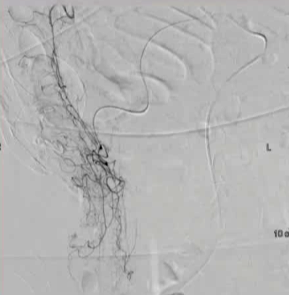

病例二

100/50 mmHg

20 μց Arterenol 170/80 mmHg

病例3 80/50 mmHg

40 μg Arterenol 170/90mmHg

|

出血点, |

PVA栓塞 |